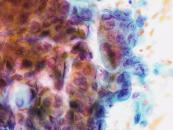

第35回日本臨床細胞学会九州連合会学会(宮崎)スライドカンファレンス症例3

種別:呼吸器

出題:福岡大学病院 病理部・病理診断科 濵﨑 慎 先生

| 年齢 | 80歳代 | 性別 | 男性 |

| 採取部位 | 左肺下葉 | 採取方法 | 腫瘍捺印細胞診 |

既 往 歴:労作性狭心症(バイパス術後)、高血圧症、高脂血症

生 活 歴:喫煙40本/日×49年

現 病 歴:労作性狭心症(バイパス術後)のフォロー中に貧血を指摘、精査中に左肺下葉に腫瘤を認め、確定診断目的で切除の方針となった。

| 正解 | 2.腺癌 |

▼選択肢及び投票結果

| 1.扁平上皮癌 | 8件 | (8.2%) | |

| 2.腺癌 | 39件 | (40.2%) | |

| 3.大細胞神経内分泌癌 | 27件 | (27.8%) | |

| 4.悪性胸膜中皮腫 | 6件 | (6.2%) | |

| 5.悪性黒色腫 | 17件 | (17.5%) | |

| 投票総数 | 97件 | (100%) |